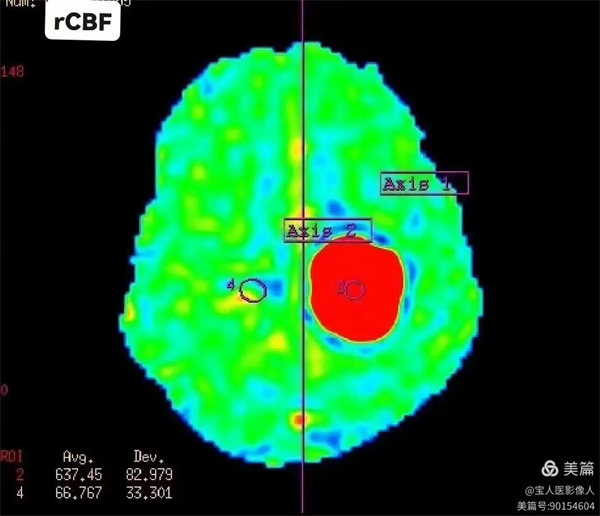

圖1:3D-ASL 局部腦血流量

病灶與正常區域局部腦血流量對照,病灶腦血流量明顯升高。(圖左下角顯示數值)

圖3:腦血流量(CBF):代表每100g腦組織內每分鐘的血流量,單位(mL/100g/min)。即血流速度。